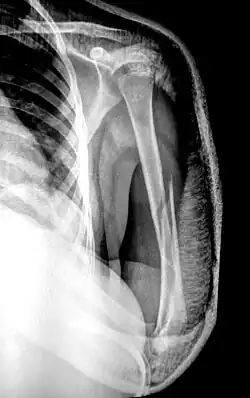

Displaced humerus fracture

Reduction is a medical procedure to restore the correct anatomical alignment of a fracture or dislocation. When an injury results in a fracture, or broken bone, the bone segments can sometimes become misaligned. This is referred to as a displaced fracture, which requires the medical procedure called reduction.[1] Some providers may refer to this as 'setting the bone'. When an injury results in a dislocation of a joint, or the misalignment of two connecting bones,[2] a similar process of reduction must be performed to relocate the joint back into normal anatomical positioning. In the case of both displaced fractures and joint dislocation reduction is required for effective healing.

There are two main categories of fracture reductions: closed reductions and open reductions. Both procedures require confirmatory imaging – such as X-ray – both before the reduction to confirm the misalignment of bones and after the reduction procedure to confirm successful achievement of anatomical positioning.